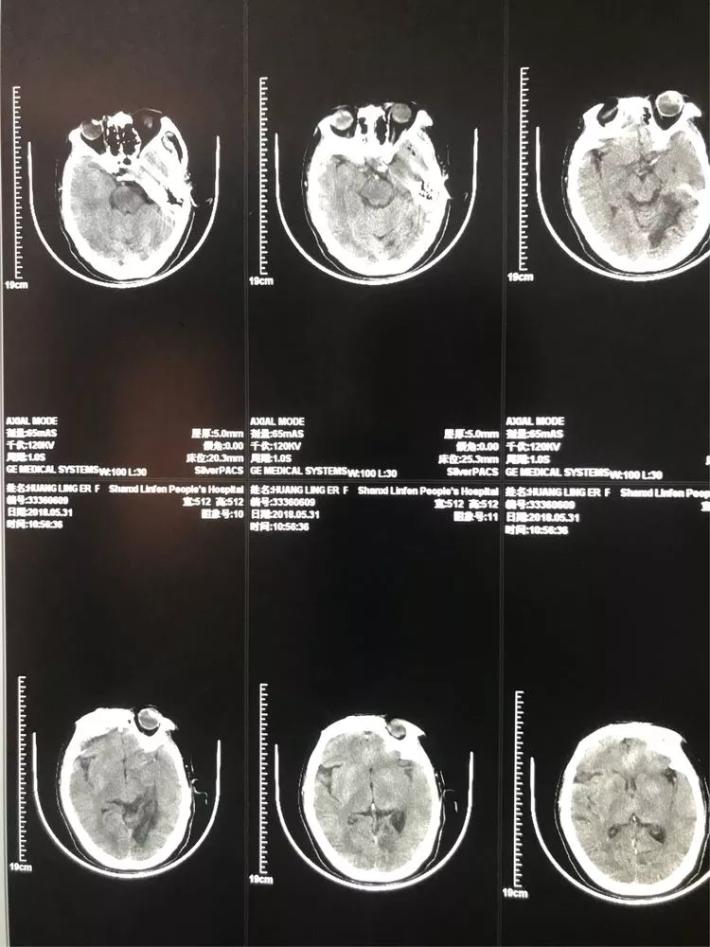

女性,61岁。主因突发左侧肢体瘫痪3小时急诊入院。颅脑CT未见出血。Nihss评分8分。急诊溶栓,同时行MRA检查。

患者女性,64岁。主因突发右侧肢体瘫痪3.5小时急诊入院。颅脑CT:未见出血。Nihss评分18分。急行静脉溶栓,同时MRA检查。